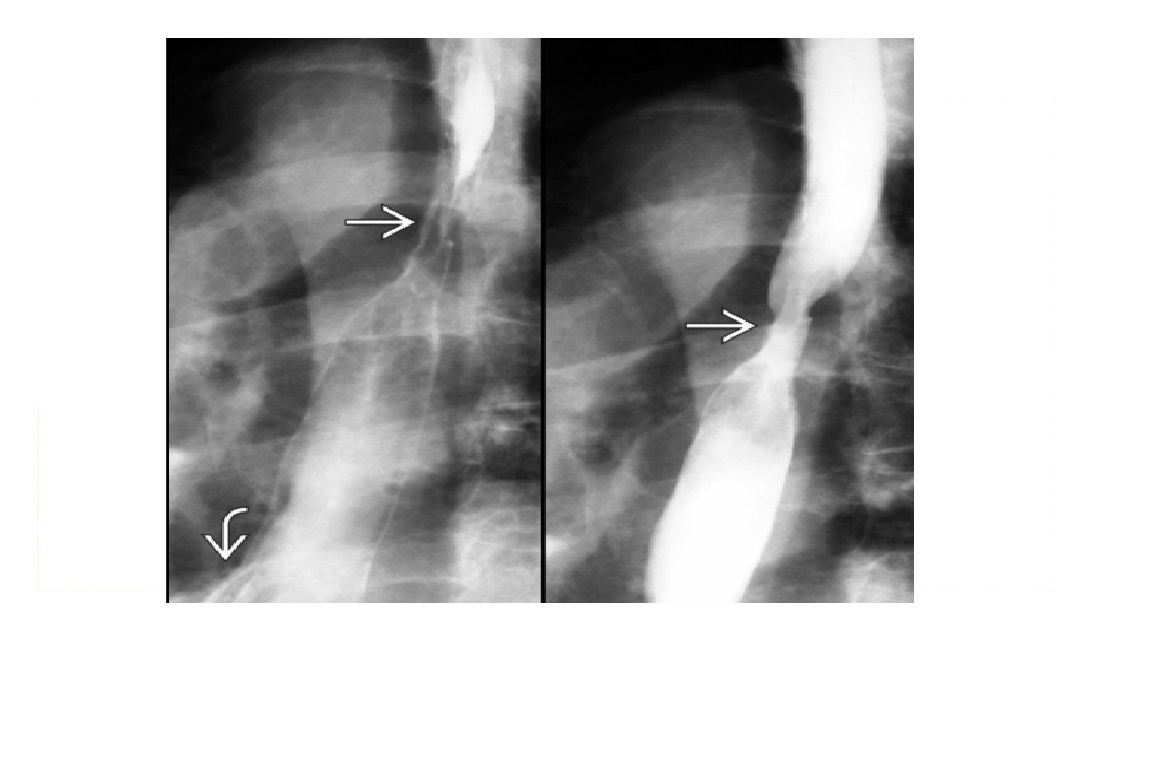

DDx for stenois of terminal ileum and features?

Crohn disease Yersina gram-negative bacterium, radiographic similar to Crohn's. resolves quickly, without stricture TB -Asymmetric wall thickening of ileocecal valve and - Cecum and terminal ileum are usually contracted (**cone-shaped cecum)** - nb Crohn's not typical for caecum -Look for signs of peritonitis/ ascites & caseated nodes - ** large linear Ulcers with elevated margins ** - Fleischner/umbrella - narrowed TI and open ileocecal valve Carcinoid Mesenteric mass (± calcification)/ desmoplastic infiltration of SB mesentery